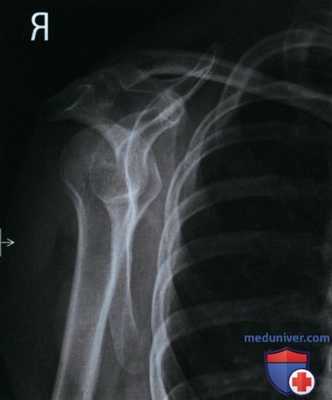

Пример анализа рентгенограммы лопатки в боковой проекции

а) Анализ. Отсутствует наложение латерального и позвоночного краев лопатки друг на друга. Позвоночный край лопатки располагается ближе к ребрам. Туловище и плечевой сустав были повернуты недостаточно. Верхний угол лопатки визуализируется ниже клювовидного отростка. Плечевая кость была отведена более чем на 90°.

б) Коррекция. Увеличьте ротацию туловища и плечевого сустава и приведите плечевую кость до угла 90° с туловищем.